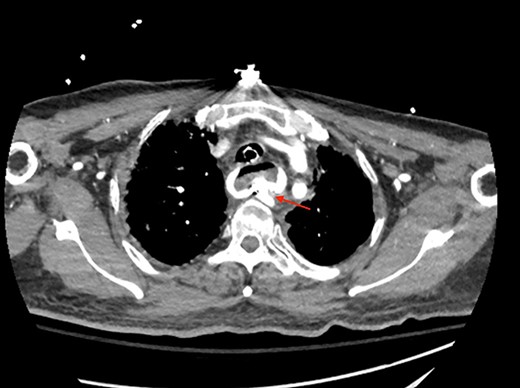

A 71-year-old male with past medical history of type 2 diabetes and hypertension presented to the emergency department at St. Joseph’s University Medical Center with severe respiratory distress. On nonrebreather, the patient’s oxygen saturation was 49%. The patient was subsequently intubated. Evaluation revealed pneumonia secondary to COVID-19 leading patient to be intubated on ventilator support for 4 weeks. During this time patient was maintained on enteral feeding through nasogastric tube, and was on gastrointestinal prophylaxis Protonix 40 mg daily for the duration of his admission. Ultimately, the patient made full recovery and was sent home; however, approximately 3 weeks later, he presented to the emergency department due to syncope. The patient experienced large-volume bright red hematemesis. He became hypotensive and was transfused three units of packed red blood cells and started on pressors. The patient was intubated and transferred to the intensive care unit (ICU) with acute blood loss anemia and hypovolemic shock. Here, an esophagogastroduodenoscopy (EGD) was performed revealing midesophageal bleed (Fig. 1). Hemostasis was achieved with clipping; however, post-procedurally, the patient again became hypotensive. Repeat EGD showed a nonbleeding esophageal ulcer with three clips in good position (Fig. 2). Computed tomography (CT) angiogram of the thorax was performed revealing an actively bleeding aberrant right subclavian artery perforating into the esophagus (Figs 3 and 4). The right subclavian artery was noted to be of normal caliber without ectasia or aneurism and the esophagus was free of any other pathology. Thoracic and vascular surgery were consulted; however, the bleed was deemed of nonsurvivable pathology due to comorbidities and current clinical status. Ultimately, the family of the patient decided to withdraw care and the patient passed.

CT thoracic angiogram showing actively bleeding aberrant right subclavian artery perforating into the esophagus (red arrow).